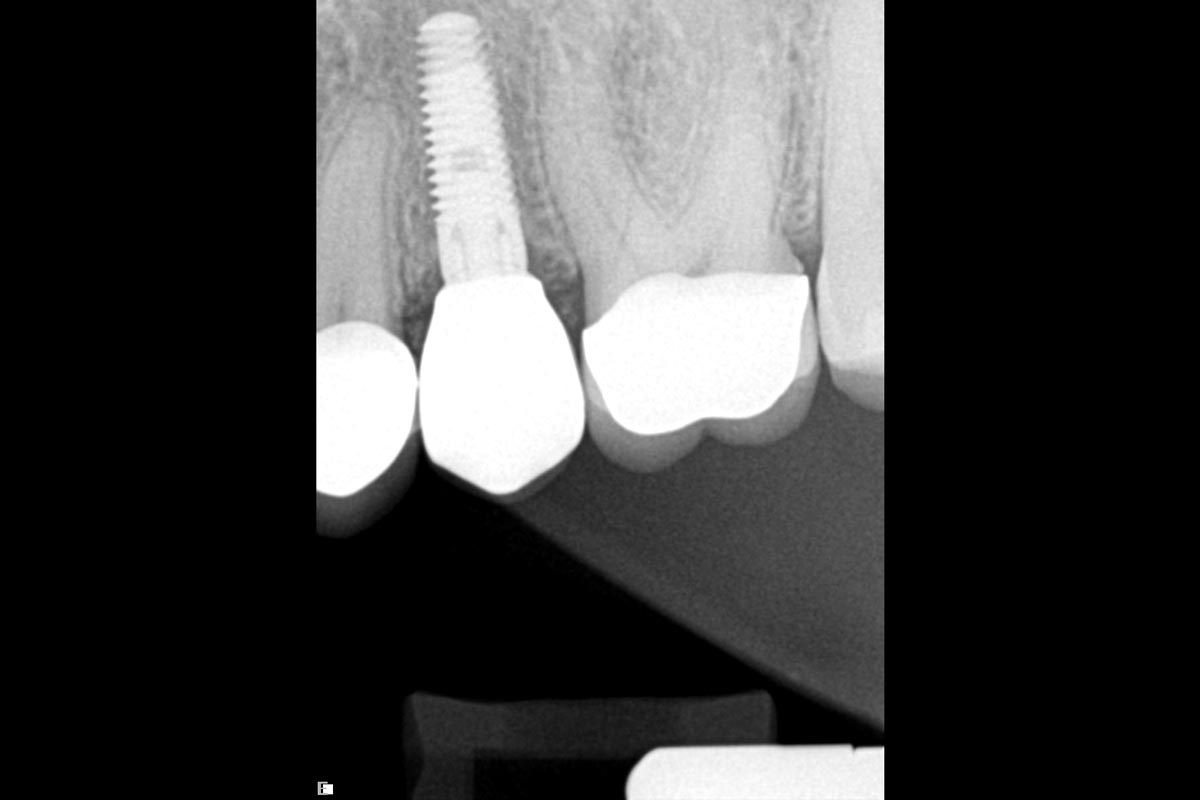

16/16 - Radiologic situation at 1 year follow upFull bone regeneration in extraction socket augmented with maxgraft® and Jason® membrane – Dr. C. Landsberg